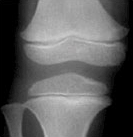

4) 같은 또래 아이들의 키보다 2표준편차 이상 작은 경우에는 성장클리닉 전문의의 진료가 필요합니다. 키가 정확히 또래 아이들보다 작은편인지 큰 편인지 진료를 통해 알아볼 수 있으며 성장판 촬영으로 골연령을 정확히 측정하는 것이 중요합니다.

| 열린경우 | 닫혀가는 경우 | 닫힌 경우 | |

| 경골 Tibia |